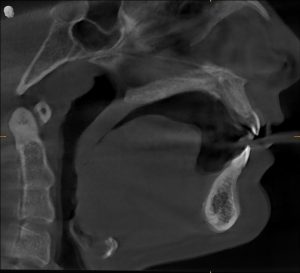

Radiographs confirmed it — his airway was constricted.

His jaw alignment had shifted to make breathing easier, but that adaptation had caused years of TMJ dysfunction.

Clinical & Radiographic Findings

- Forward head posture and low tongue position

- Narrow pharyngeal airway space

Radiographs confirmed increased airway space and balanced joint position.